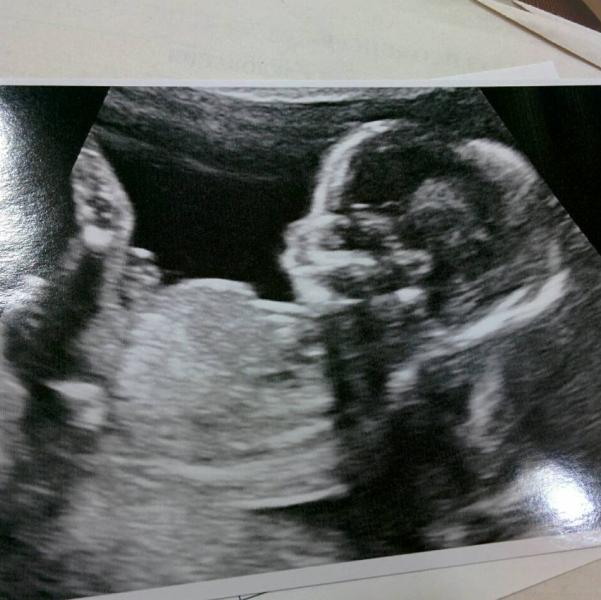

Были на УЗИ...

Крохотные ручки, по пять пальчиков на каждой, крохотные ножки... Сердечко, мозжечок, позвоночник, ребрышки. Все измерили, посчитали, сфотографировали😍

Ну и... кажется, у нас девчуля😄

Поэтому решила для успокоения сходить дополнительно, так совсем другое дело, пока всё-всё не посмотрела и нам не показала не отпустила нас) Ну и пол как приятный бонус😄

Нам с мужем очень понравилось, смотрели больше 30 минут, всё очень внимательно, всё объяснили. В итоге куча фотографий и видео на диске, их не смотрели пока)